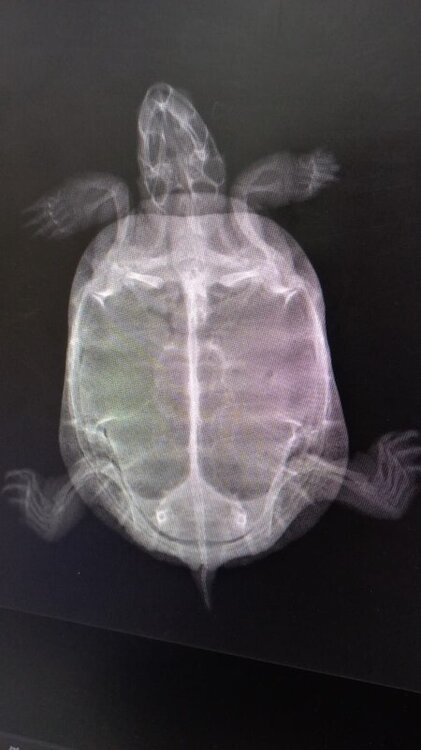

Обращались. В 1-м вет кабинете прописали байтрил 5% 0.12 мл на 5 дней и какие-то витамины жидкие перорально (не знаю какие, мне дозировано набрали в шприцы). Поставили байтрил дважды, черепашка очень плохо переносила, были судороги. Я нашла ваш форум, прочитала что ставить надо 2.5%, по калькулятору тут же высчитали дозу 0.13, поставили один раз, неизвестные витамины прекратили давать. Пошли в другую клинику, там сделали рентген (жидкость в легких), нам снизили количество байтрила 2.5 до 0.06 мл - еще 4 дня, и назначили Фуросемид 0.06 * 3 укола. Ставили все уколы в.м. в передние лапки. Состояние черепахи без изменений. Через 5 дней - повторный прием и рентген, отсутствие положительной динамики ( в описании рентгена: папуллезные включения в паренхиме легких, предположительно метастазы), прописали Преднизолон 5 мг 1/8 таблетки 2 раза в сутки * 14 дней. Преднизолон не давала и не хочу. Помогите, пожалуйста.